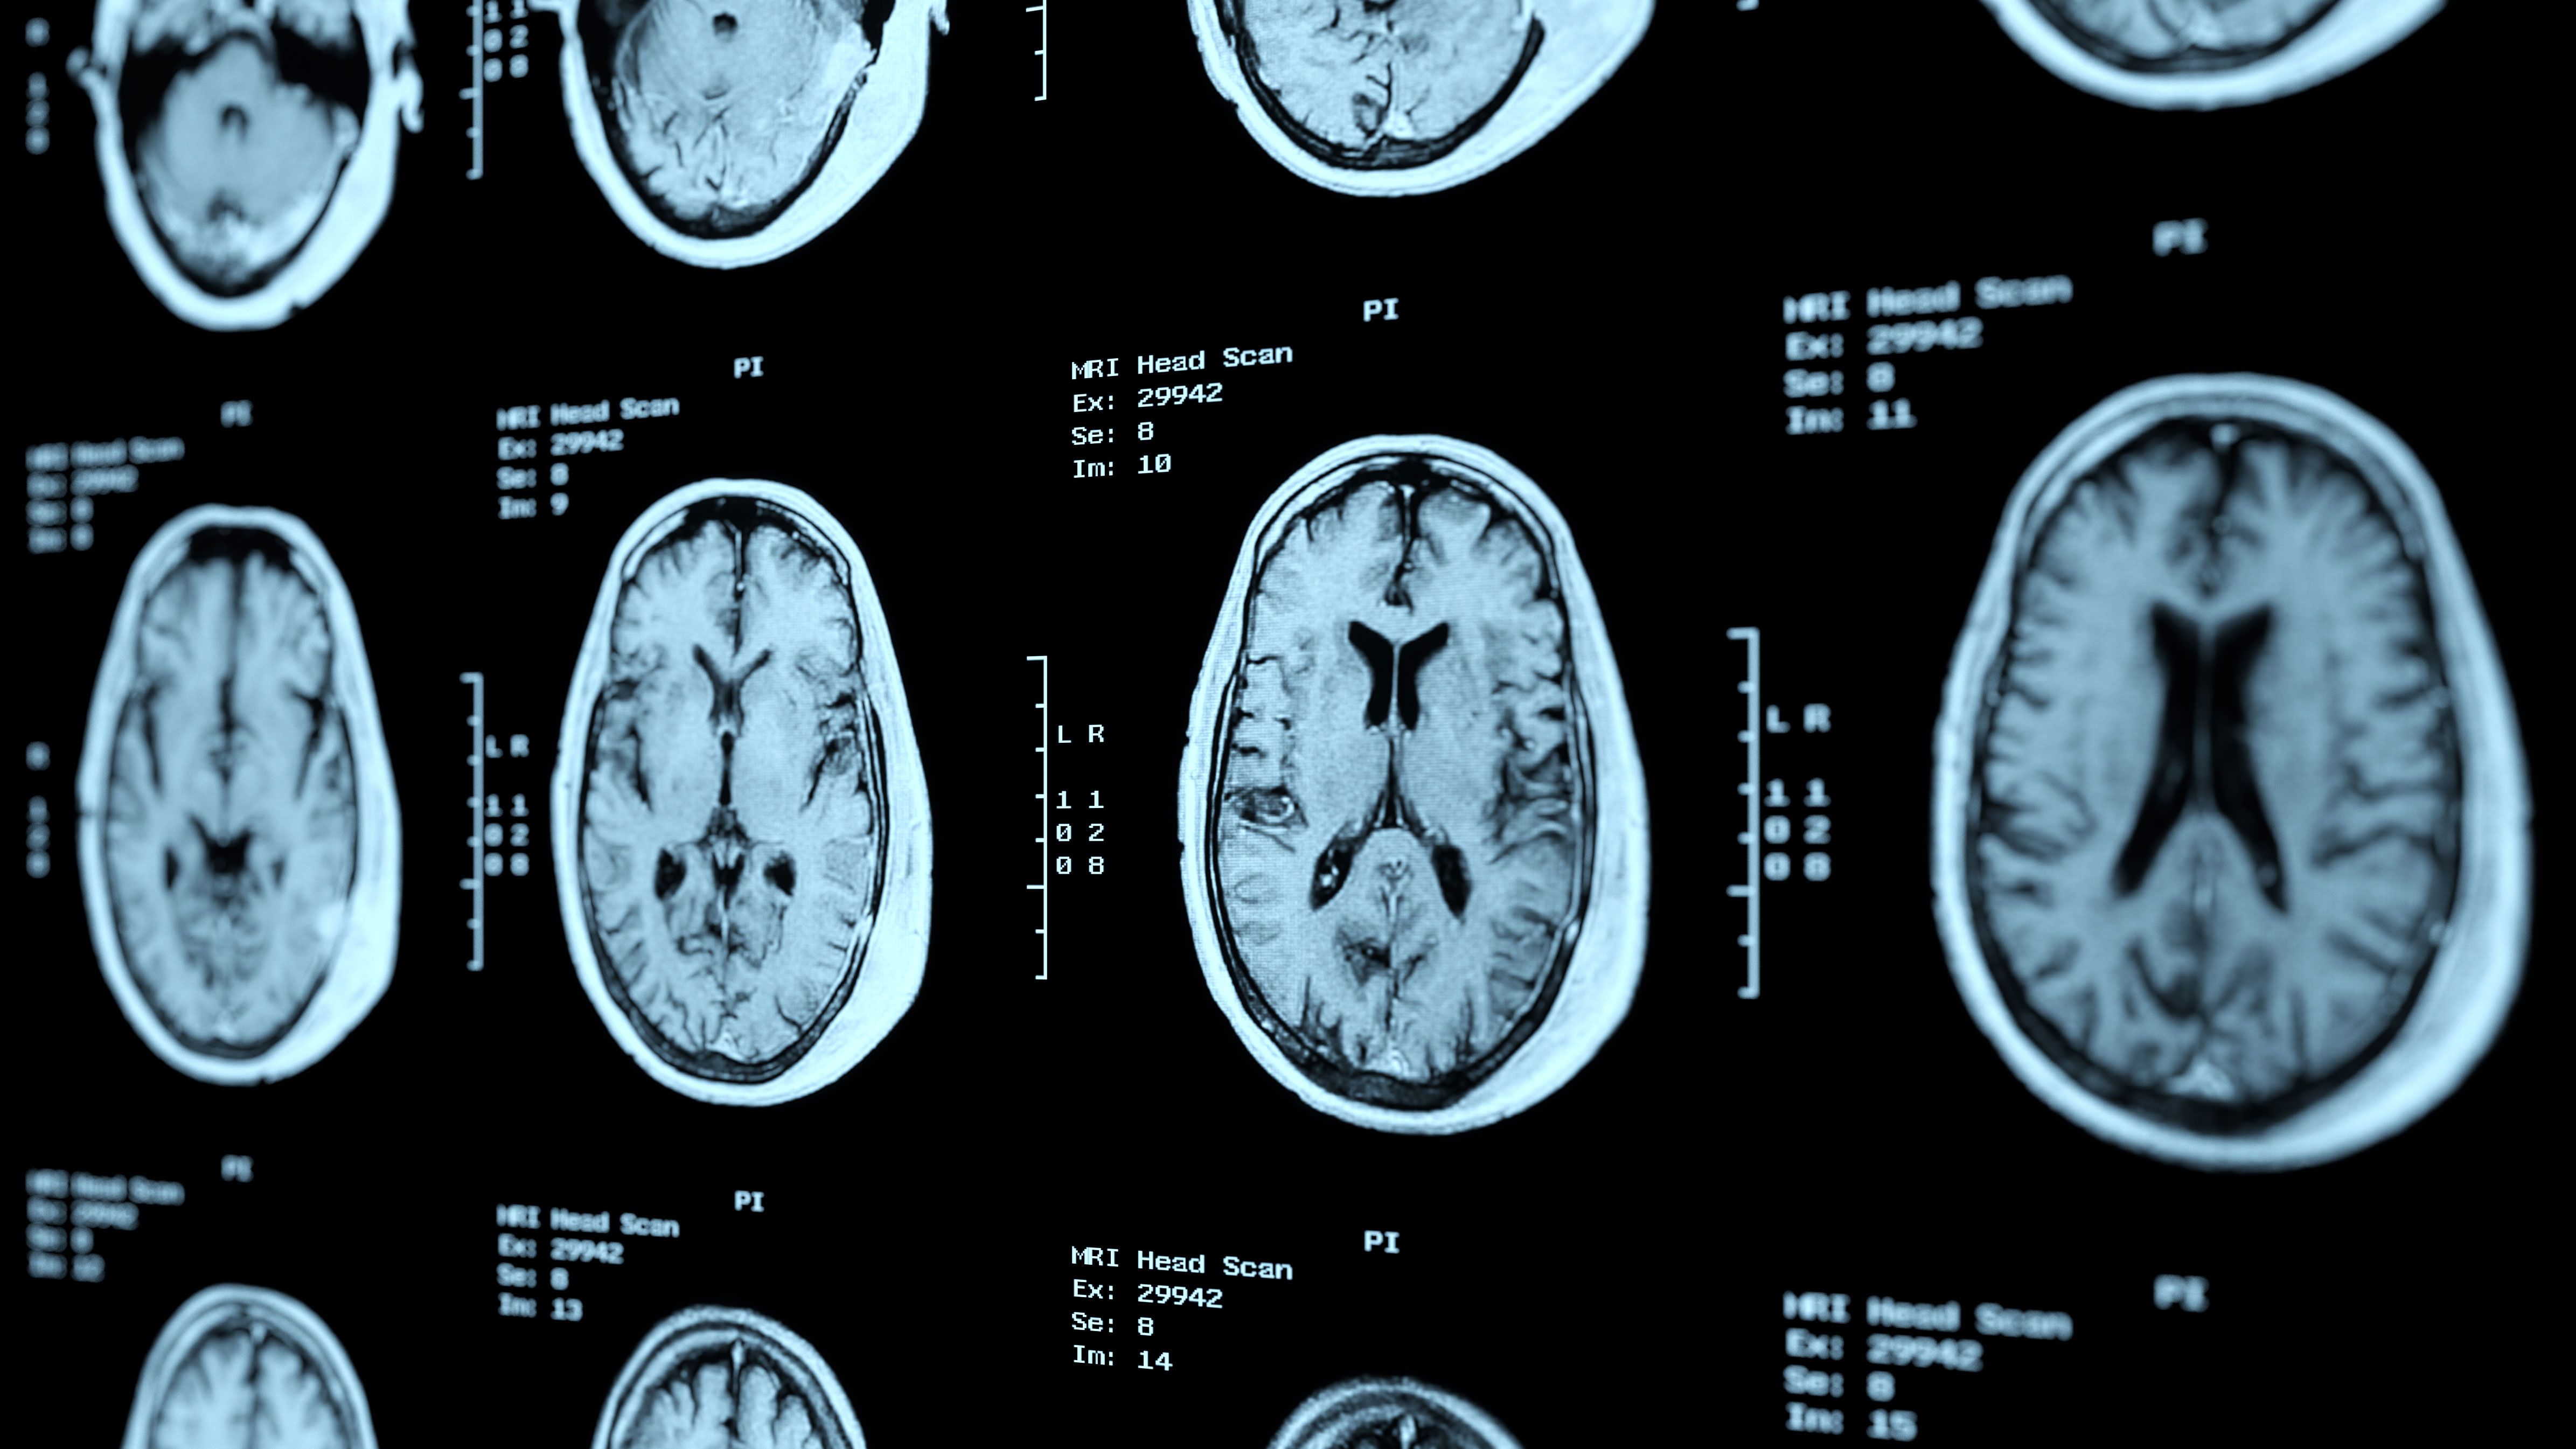

Cte statistics is the nces reporting system for national information on career and technical education (cte) and workforce preparation. Caucastransexpress (cte) started operating as an international freight forwarder in tbilisi, georgia in 1999. In this article, we will see in detail about how to create and use the cte query starts with a with and is followed by the expression name. Sanjay gupta explains the causes and symptoms of chronic traumatic encephalopathy, more commonly known as cte. Cte is a progressive degenerative disease of the brain commonly found in people with a history of repetitive brain trauma.

Cte is a progressive degenerative disease of the brain commonly found in people with a history of repetitive brain trauma. What does cte abbreviation stand for? Duyurular cte haberler kurum haberleri basında cte. Caucastransexpress (cte) started operating as an international freight forwarder in tbilisi, georgia in 1999. Data taken after this date will automatically have the new correction applied; Toplam 28 cte haberi, videosu, fotoğrafı ve yazar yazısı yer almaktadır. Chronic traumatic encephalopathy (cte) is a neurodegenerative disease linked to repeated blows to the head. I wonder if oprah asked michael jackson what cte on his shoulders meant when she interviewed him in 1993? Is there something i am missing or not understanding well? It has also been found in athletes who did not play sports. Cte has been known to affect boxers since the 1920's (when it was initially termed punch drunk cte is not limited to current professional athletes; Our spring 2020 cte virtual office hours have ended. The cosmetology program may have classes starting each week.